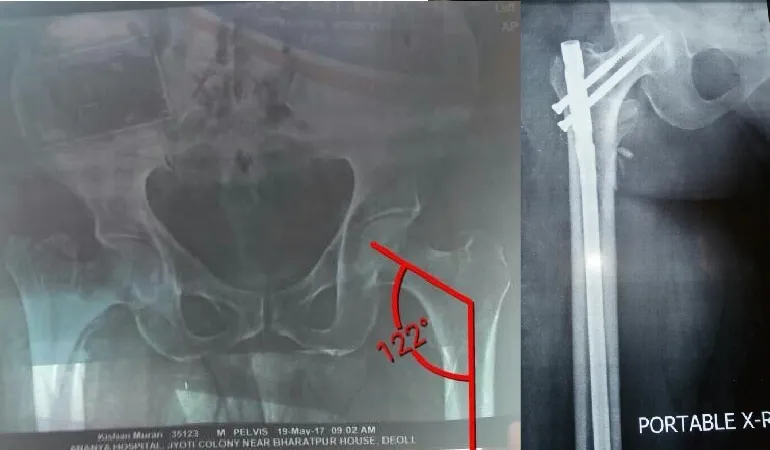

His clinical journey is defined by an extraordinary milestone of performing more than 10,000 successful surgeries. This vast experience ranges from routine fracture care to some of the most complex joint replacements and arthroscopic procedures in the region. Dr. Shah’s practice at Vedant Hospital, Gota, is built on the pillars of precision, ethical practice, and deep-rooted compassion.